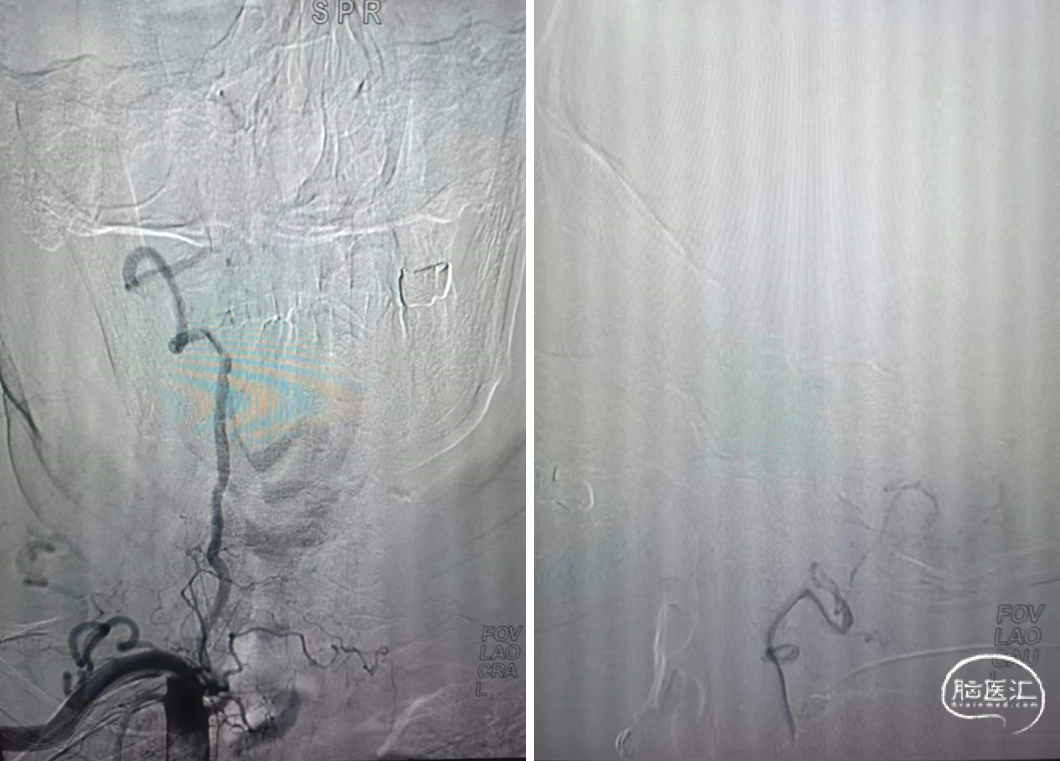

XT27微导管到位

支架导管到位

支架到位

回撤支架输送杆

4.5mm*20mm自膨支架释放

复查造影